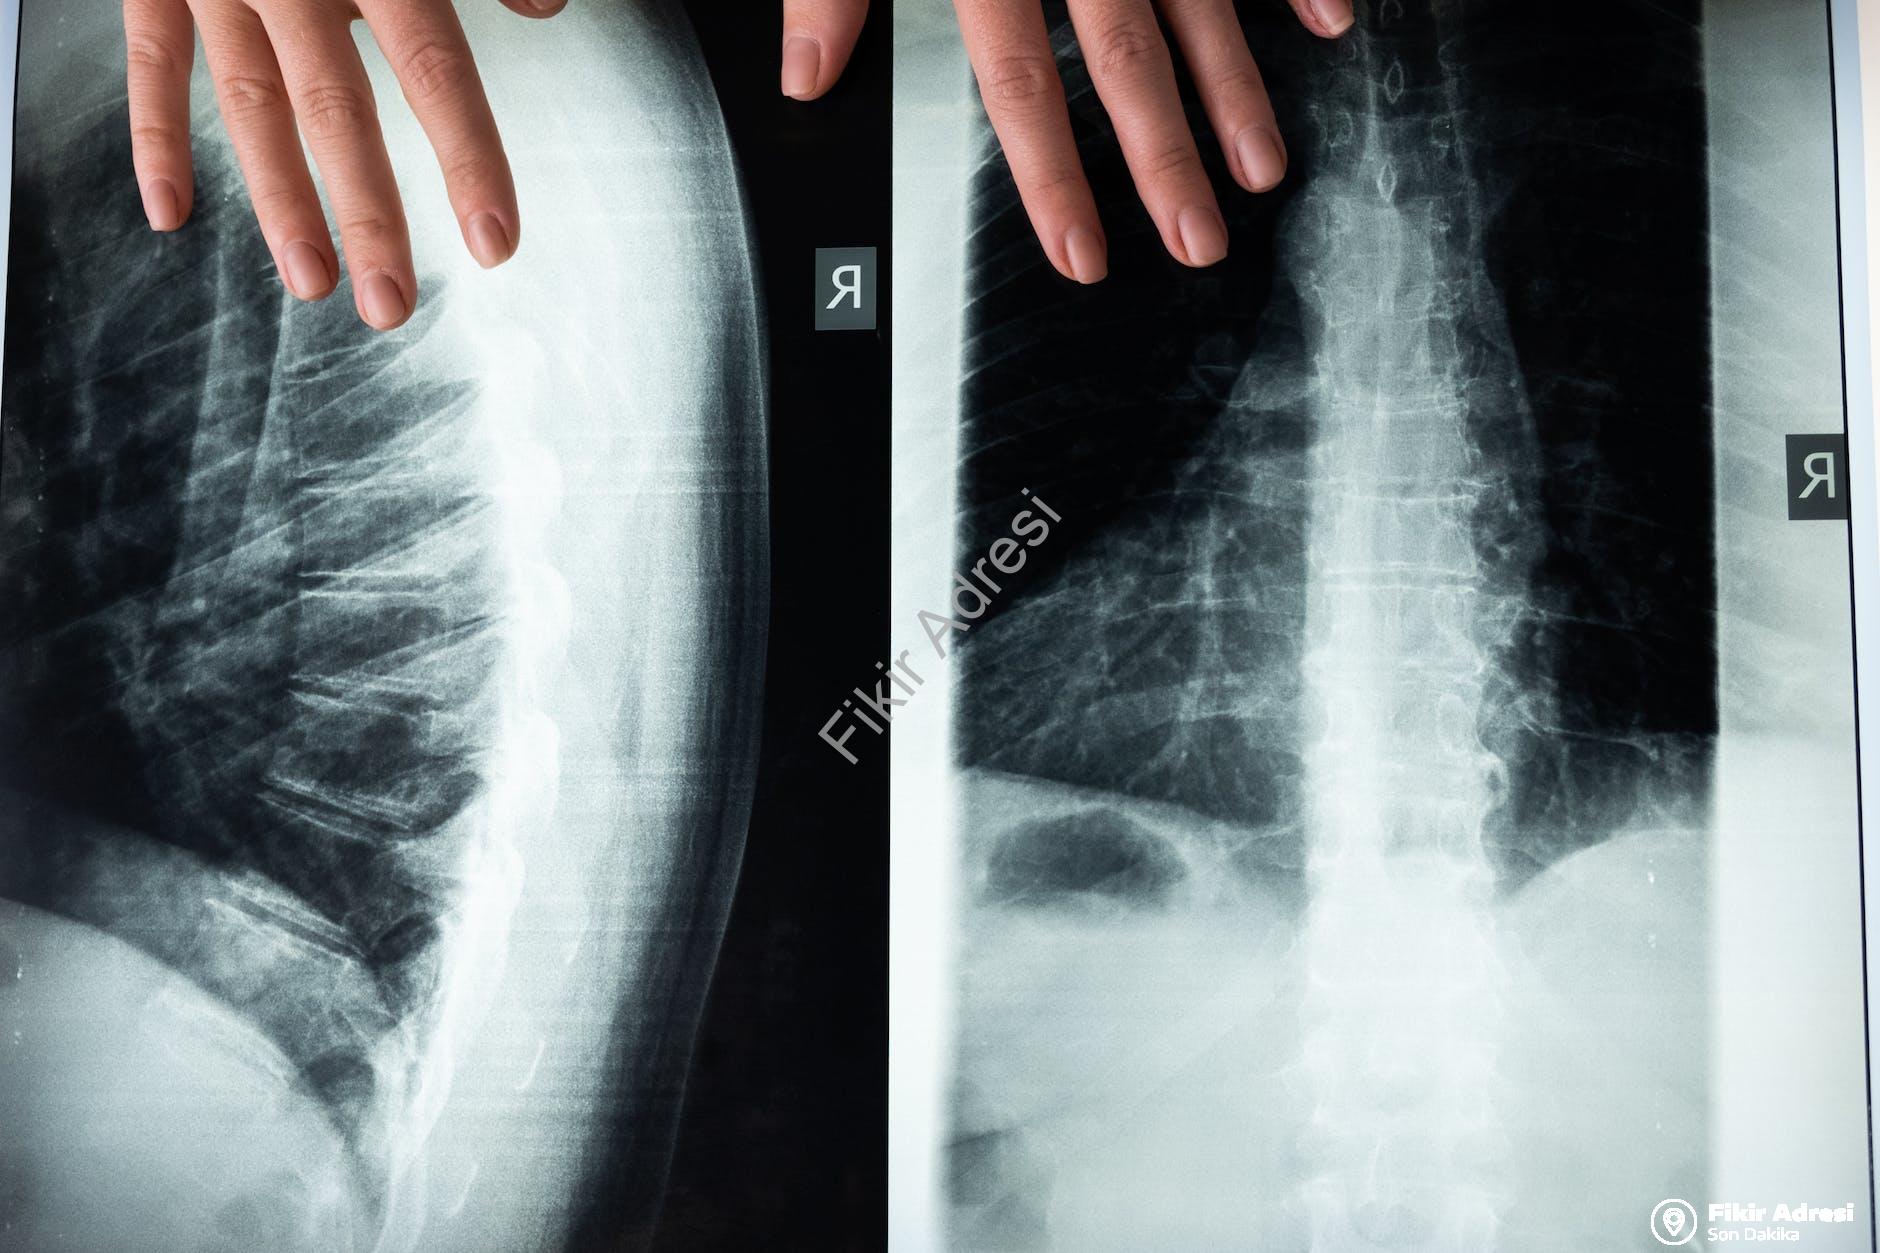

Boyun fıtığı, günümüzde birçok insanın karşılaştığı bir sağlık sorunudur. Boyun ağrısı, sertlik, baş ağrısı gibi belirtilerle kendini gösteren boyun fıtığı, yaşam kalitesini olumsuz yönde etkileyebilir. Ancak, şaşırtıcı bir şekilde, boyun fıtığı tedavisinde elde edilen sonuçlar oldukça umut vericidir.

Boyun fıtığı, birçok insanın yaşadığı bir sağlık sorunudur. Geleneksel tedavi yöntemleri arasında cerrahi müdahale yer alırken, son yıllarda ameliyatsız tedavi seçenekleri de popülerlik kazanmıştır. Bu alternatif yöntemler, hastalara daha az invaziv bir seçenek sunarak büyük bir avantaj sağlamaktadır.

Boyunda fıtık, boyun omurlarının arasında yer alan disklerin dış tabakasının zedelenmesi sonucu içeriklerinin dışarı doğru çıkması durumudur. Bu durum, sinir köklerine baskı yaparak ağrı, uyuşma ve güç kaybına neden olabilir.